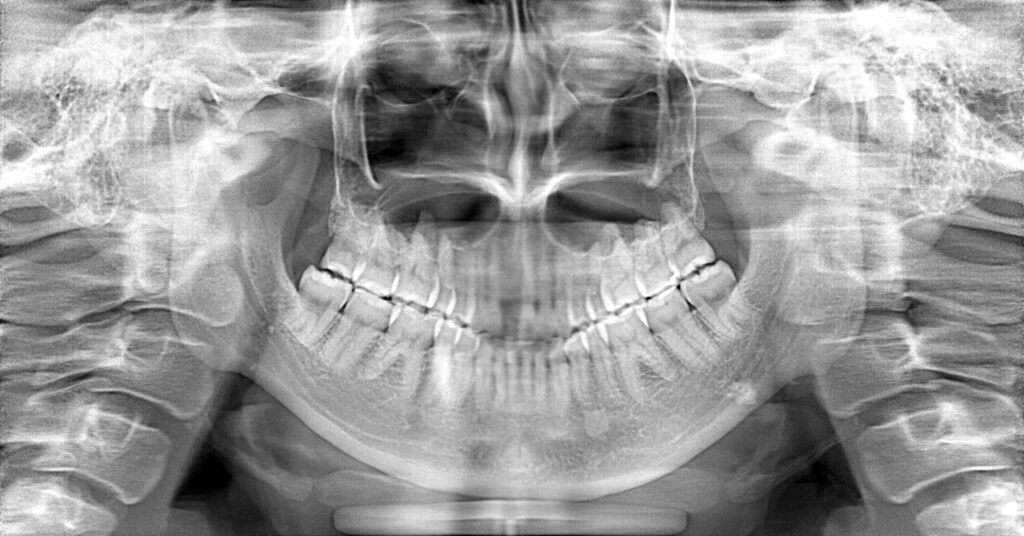

症例一覧 インプラント症例2 2024.11.25 治療内容インプラント主訴前歯事故で折れたのでインプラント治療を行いたい費用¥946,000(1本)治療期間7ヶ月 インプラント症例3 前の記事 インプラント症例1 次の記事